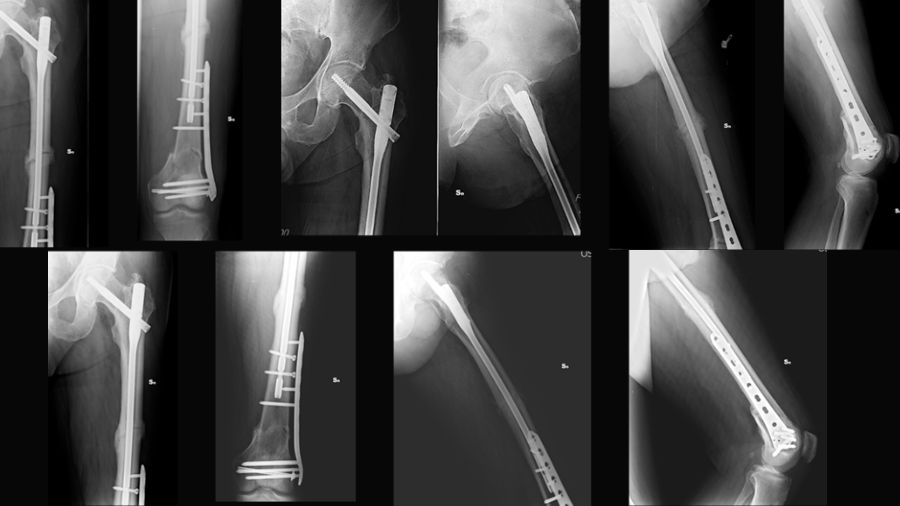

This case report describes a high-energy trifocal femoral fracture (intracapsular femoral neck, femoral shaft, and complete distal articular femur) treated with an intramedullary nail, free cannulated screws, and a LISS plate.

This combination of implants, not previously reported in the literature, allowed for an anatomical reduction with absolute stability of the distal periarticular fracture and a functional reduction with relative stability in the other two fractures (shaft and femoral neck).

After resolving the pulmonary complications, the definitive surgery was performed in a single stage, step by step:

- Kirschner wires were used to stabilize the femoral head, preventing further displacement

- Cannulated screws were applied to fix the intra-articular distal femoral fracture

- A nail with static distal locking was inserted

- A LISS plate was applied

As seen in the following images, all fracture sites healed with near-complete functional recovery, and no complications or deficits were reported. The full clinical case, including a video demonstrating the patient's functional recovery, can be accessed via this link.

We used an antegrade reconstruction nail for the femoral neck and diaphyseal fractures, cannulated screws for the distal intra-articular fracture, and a LISS plate for the supracondylar femur fracture. This combination prioritizes articular fractures with direct reductions and optimally treats the femoral shaft with intramedullary nailing.